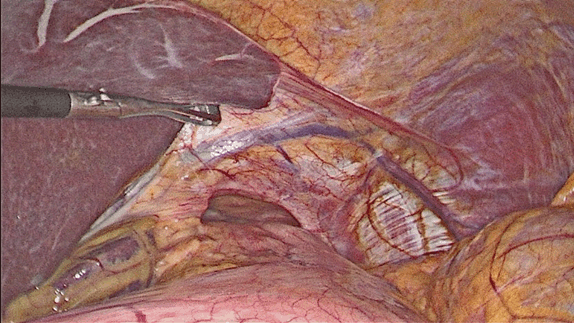

A 72-year-old female was admitted in our institution for surgical repair of GERD with a large symptomatic hiatal hernia. Conservative treatment, for more the one year, did not show any significant improvement of the regurgitation, dysphagia, chronic cough and oral intake limitations. She had a past history of arterial hypertension, thrombocytosis, chronic heart failure and osteoporosis. Endoscopic and contrast X-ray examinations showed multiple duodenal diverticula and a large, type II hiatal hernia containing 1/3 of the stomach into mediastinum, with diameter of 10 cm and reflux disease Grade II by Savary-Miler classification. Laparoscopy confirmed large hiatal hernia with diastasis and sclerosis of the diaphragmatic crus (Figure 1).

Nissen’s fundoplication was performed along with relaxing incision of the left crus. Omiramesh® (Ethicon) 10x15 cm mesh was placed with Secure strap® (Ethicon, Norderstedt, Germany) to the diaphragm (Figure 2) and (Figure 3).

Figure 1: Intraoperative view.

Figure 2: Instrument against tissue for fixation of the mesh – thin down the tissue and increase the potential for underlying damage.